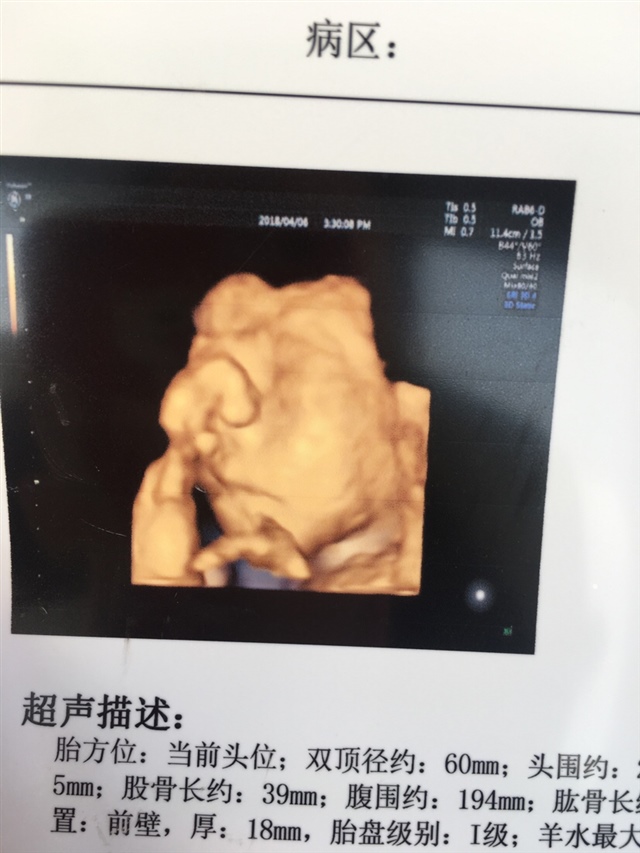

孕33周+3天

接健康男宝宝已在我腹中,保佑平平安安足月顺产出生